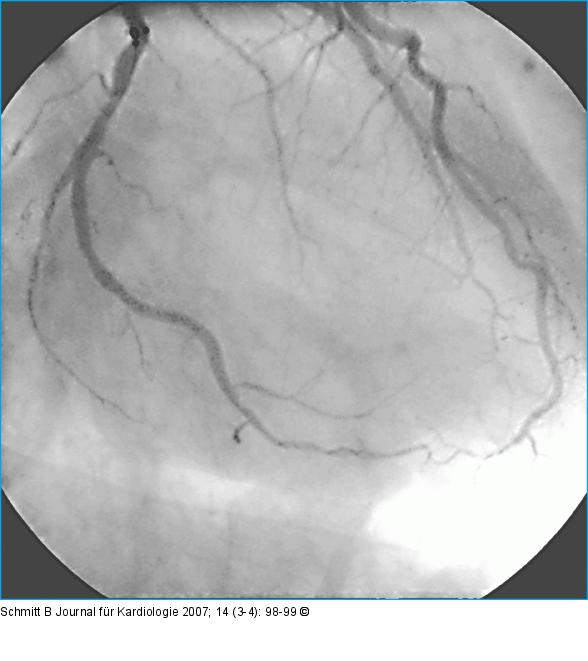

Abbildung 4: Rekanalisation - Ballondilatation

Nach erfolgreicher Rekanalisation und Ballondilatation. |